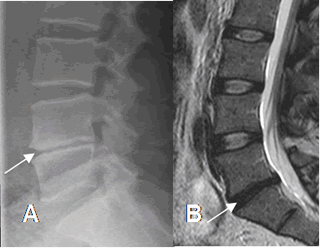

Fig 33. Cambios degenerativos del disco.

A: Rx lateral y B: RM sagital en T2. Disminución de los espacios intervertebrales, por proceso degenerativo.